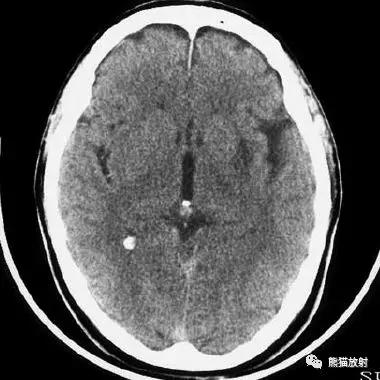

右侧大脑前动脉供血区部分梗死

右侧大脑后动脉供血区梗死

双侧大脑后动脉供血区梗死